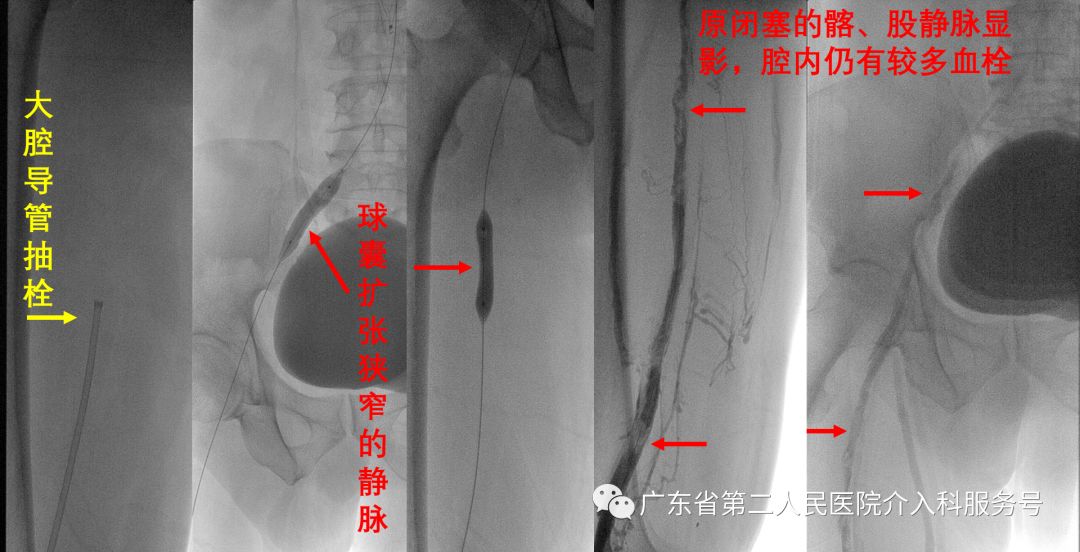

第一次大腔导管抽栓与球囊扩张狭窄的静脉后造影显示:原闭塞的髂、股静脉显影,腔内仍有较多血栓(如下图)。